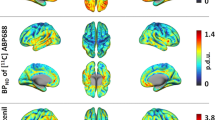

The mean age and weight of the study sample (n = 12 men) were 33 ± 8 years and 72 ± 13 kg, respectively. The regional brain mGluR5 availability in this sample was in agreement with the known distribution of mGluR5 in humans, with highest availability in the cingulate cortex (anterior and posterior), striatum and prefrontal regions and lowest availability in cerebellum and pons (Fig. 4). Then it decreased slowly and linearly until the end of the acquisition. We obtained good quality MR spectra from all subjects allowing reliable quantification. The mean glutamate and glutamine levels in the ACC were 5.84 ± 0.64 and 3.40 ± 0.93, respectively. Then, metabolites were quantified relative to creatine (Cr) and the mean Glu/Cr, Gln/Cr, and Glx/Cr levels were 1.12 ± 0.12, 0.64 ± 0.14, and 1.75 ± 0.18, respectively (Fig. 5). To test for an interaction of mGluR5 density and glutamate concentration, we correlated the [18F]FPEB BPND with Glu/Cr, Gln/Cr, and Glx/Cr ratios in the ACC. In the whole sample, ACC BPND did not correlated with ACC glutamate (r = 0.51; p = 0.09), glutamine (r = −0.46; p = 0.13) or Glx (r = −0.035; p = 0.92) (Fig. 5).